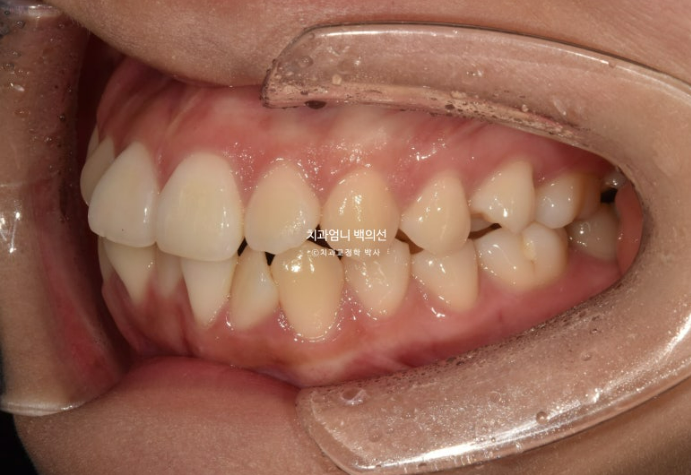

23년 12월 앞니 부분교정을 위해 오신 분입니다.

앞니 두 개가 크기도 하고 내려와 있습니다.

파란 화살표에 작은 어금니 덧니도 보입니다.

아래 앞니가 많이 삐뚭니다.

어금니 교합이 그리 좋은 편은 아니지만 환자분은 씹는데 불편함을 못 느끼는 상태였고 앞니 배열만 원하셨습니다.